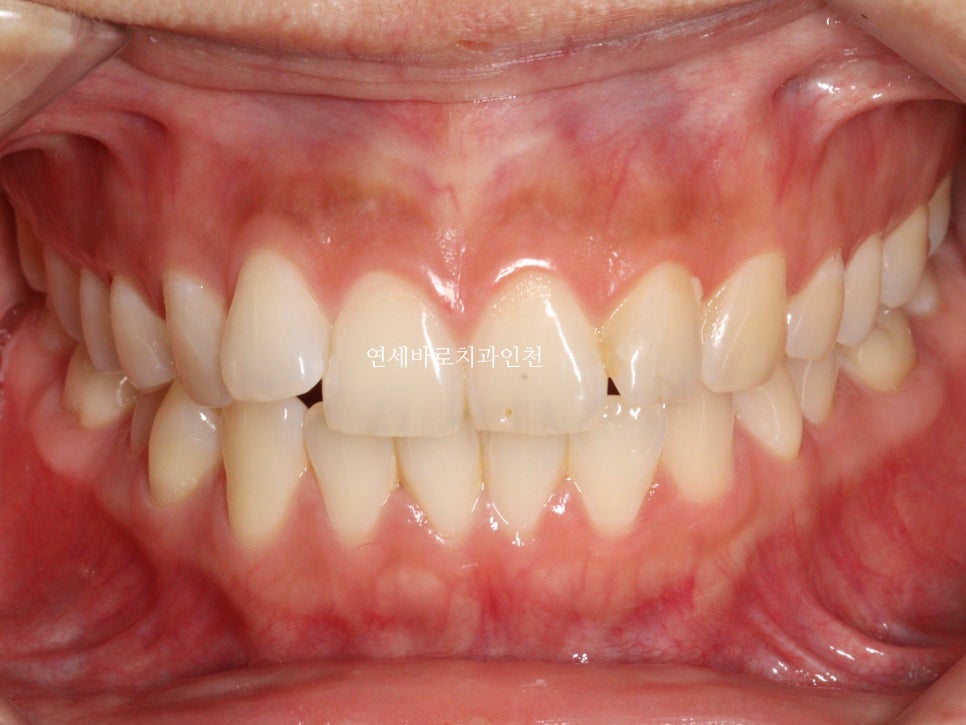

치열이 삐뚤삐뚤하신 상태입니다.

치열의 배열 및 골격적인 분석 결과 무턱과 입술이 자연스럽게 다물어 지지 않는 것도 발견되었습니다.

위 사진은 어느정도 힘을 주고 찍은 사진입니다.

교정이 마무리되고 보면 문제없죠?

이분은 재제작없이 끝냈습니다.

하지만 보다 나은 안모의 개선을 위해 comprehensive옵션을 선택, 미니스크류를 동반하여 치료를 마무리한 환자분 입니다.